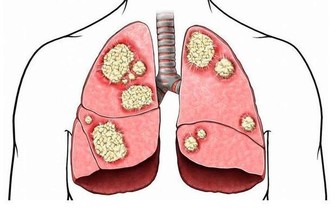

對肝威脅最大的是肝炎、肝硬化和肝癌。經常過量飲酒的人群,肝硬化和肝癌的機會比一般人高得多。